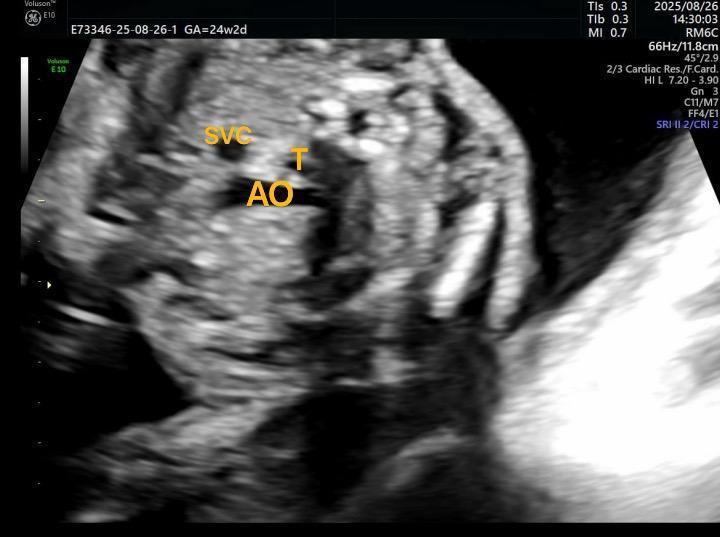

“三血管气管切面有彰着很是在现,怀疑是大动脉转位,单纯有余性。”在普瑞姆妈四维查验当作的误差,一场专科、急切的诊断,正在超声科悄然进行。

同期,在超声筛查下,单纯有余性大动脉转位“四腔心”“五腔心”等多个要道切面,均无很是辅导,很是结构更为掩盖,频频容易漏诊。需要训诲丰富的超声科医师,锐利发觉微小很是,详尽跟踪主、肺动脉溯源器官,筛查难度更大。

“诊断不错细目接下来的筛查观点,进行有观点性的精确排畸。”鲁亚兰示意。这两例即是通过超声跟踪心房心室一语气、心室大动脉一语气、室阻隔是否竣工等,最终确诊了单纯有余性大动脉转位,为重生家庭的优生优育、宝宝救治决策提前定制得到了可贵的时辰。